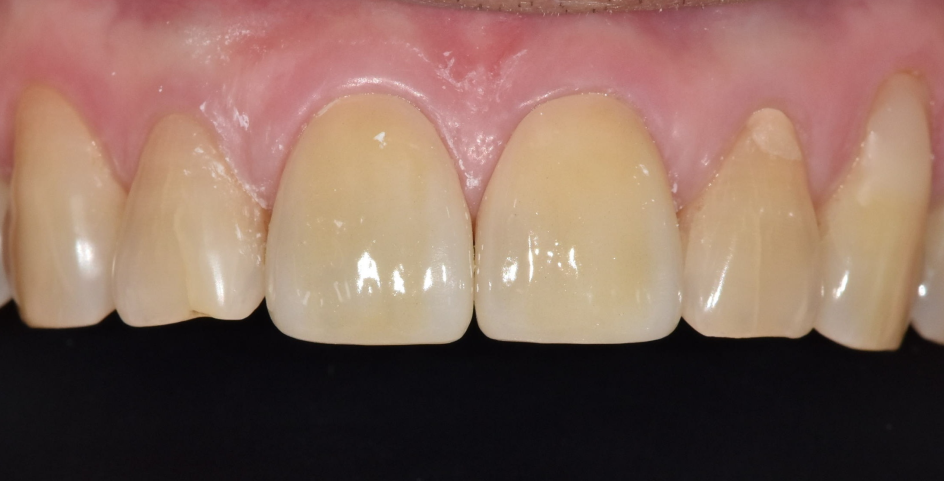

치아를 보는 순간 알 수 있었던 사실 하나는

"아, 이분 딱딱한 음식 좋아하시는구나."였습니다.

위아래 치아의 씹는 면이 전반적으로 다 닳아있었거든요.

특히 문제는 금이 간 앞니였습니다.

240605

보통은 위 앞니가 아래 앞니를 살짝 덮으면서,

가위처럼 음식을 잘라내는 구조를 이룹니다.

하지만 이 분은 위아래 앞니 끝과 끝이

정면으로 맞닿아 있었습니다.

식사할 때마다 마치 못 위에 망치를

계속 내리치듯, 앞니 끝끼리 정면으로 부딪히고 있었던 겁니다.